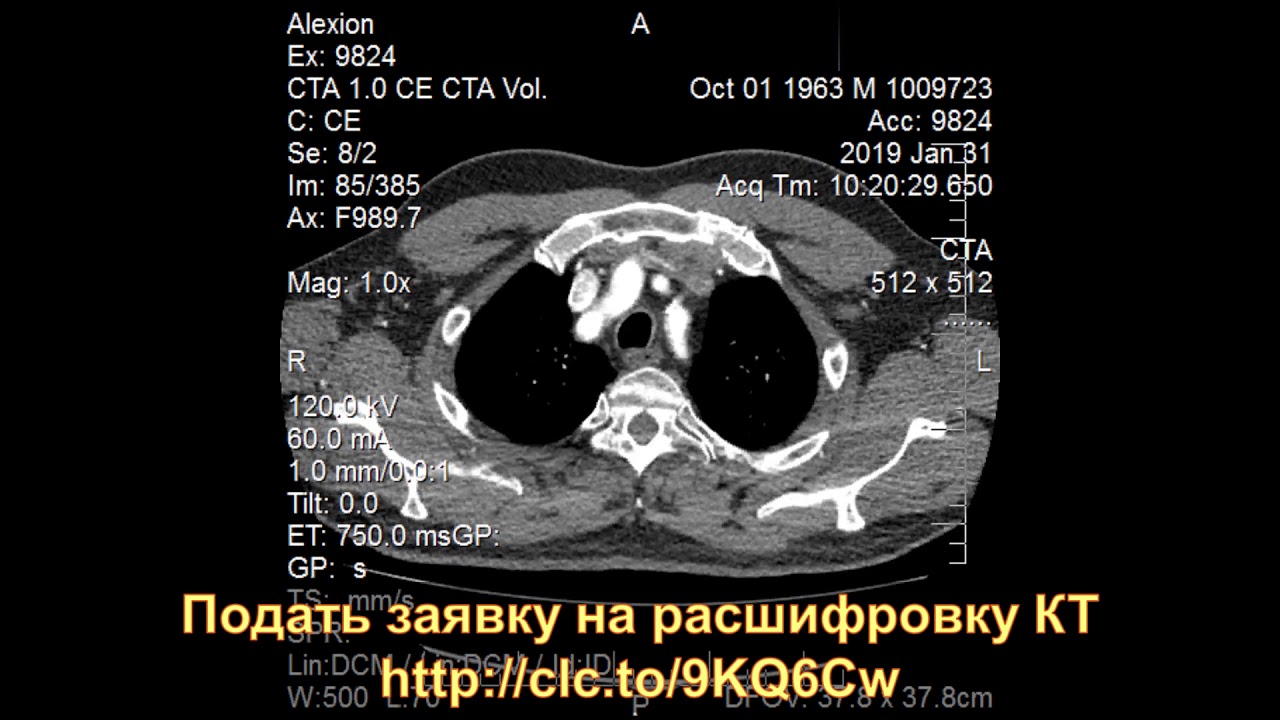

Что покажет МСКТ и КТ-ангиография аорты при коарктации

- Отмечаются те же изменения, что и при проведении МРТ

- Вследствие лучевой нагрузки применение КТ у детей и молодых пациентов должно быть обосновано.

Что показывает КТ аорты?

Расшифровка результатов. Протокол КТ содержит описание всех увиденных сосудистых структур, аорты и ее ветвей, их точный размер. Помимо этого специалист указывает все обнаруженные нарушения: аневризмы, пороки развития, расслоение сосудистой стенки, травмы, воспаления, бляшки атеросклероза и другие изменения.